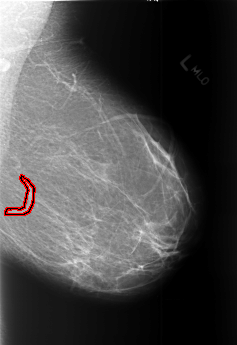

FILE: B_3453_1.LEFT_MLO.OVERLAY

TOTAL_ABNORMALITIES 1

ABNORMALITY 1

LESION_TYPE MASS SHAPE TUBULAR MARGINS N/A

ASSESSMENT 2

SUBTLETY 3

PATHOLOGY BENIGN_WITHOUT_CALLBACK

TOTAL_OUTLINES 1

BOUNDARY